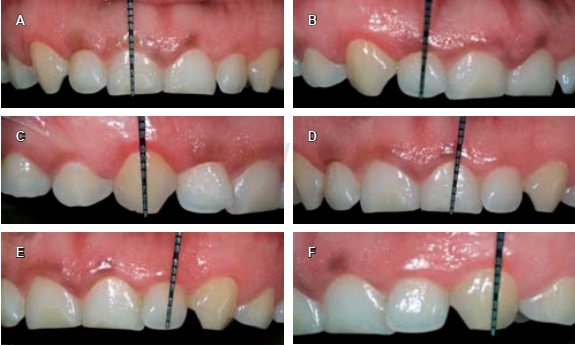

En la anamnesis realizada no refiere enfermedades patológicas, por lo que se considera como paciente aparentemente sana. En la evaluación clínica inicial se le realiza el sondeo periodontal dando como diagnóstico: erupción pasiva alterada tipo 1, subgrupo B en el sector anterior superior (del 1.3 a 2.3 según nomenclatura FDI) (Figura 1). El plan de tratamiento indicado es alargamiento de corona estético en una sola cita utilizando como herramienta radiológica de apoyo el CBCT con el objetivo de lograr precisión en la ubicación de los siguientes parámetros: tamaño de corona anatómica, longitud de UCE-cresta ósea y cantidad de tejido gingival a eliminar durante el procedimiento quirúrgico.

Figura 2 Medida de las coronas clínicas de piezas 1.3, 1.2, 1.1, 2.1, 2.2, 2.3 con una sonda periodontal milimetrada.